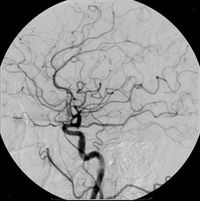

تستخدم المواد المظللة في التشخيص الطبي، لتشخيص تغيرات تحصل في أعضاء معينة في الجسم كالأوعية الدموية مثلاً التي هي في حالتها الطبيعية ممتلئة بالدم، الذي له كثافة إشعاعية مشابهة لكثافة النسيج المحيط (عضلات أو أنسجة رابطة) وبالتالي لا يمكن رؤية الأوعية الدموية على صورة الأشعة. فيتم حقن المادة الملونة في هذه الأوعية الدموية، مما يرفع الكثافة الشعاعية للمحتوى الوعاء الدموي ـ هنا على سبيل المثال ـ ويجعل محتوى هذا الوعاء ومساره واضحاً. كما هو مبين في الصورة التي تظهر القسطرة. وهذا المبدأ يمكن استخدامة في إظهار محتويات كثير من "الأوعية" في جسم الإنسان، مثل الجهاز الهضمي أو المثانة والمجاري البولية ... الخ.